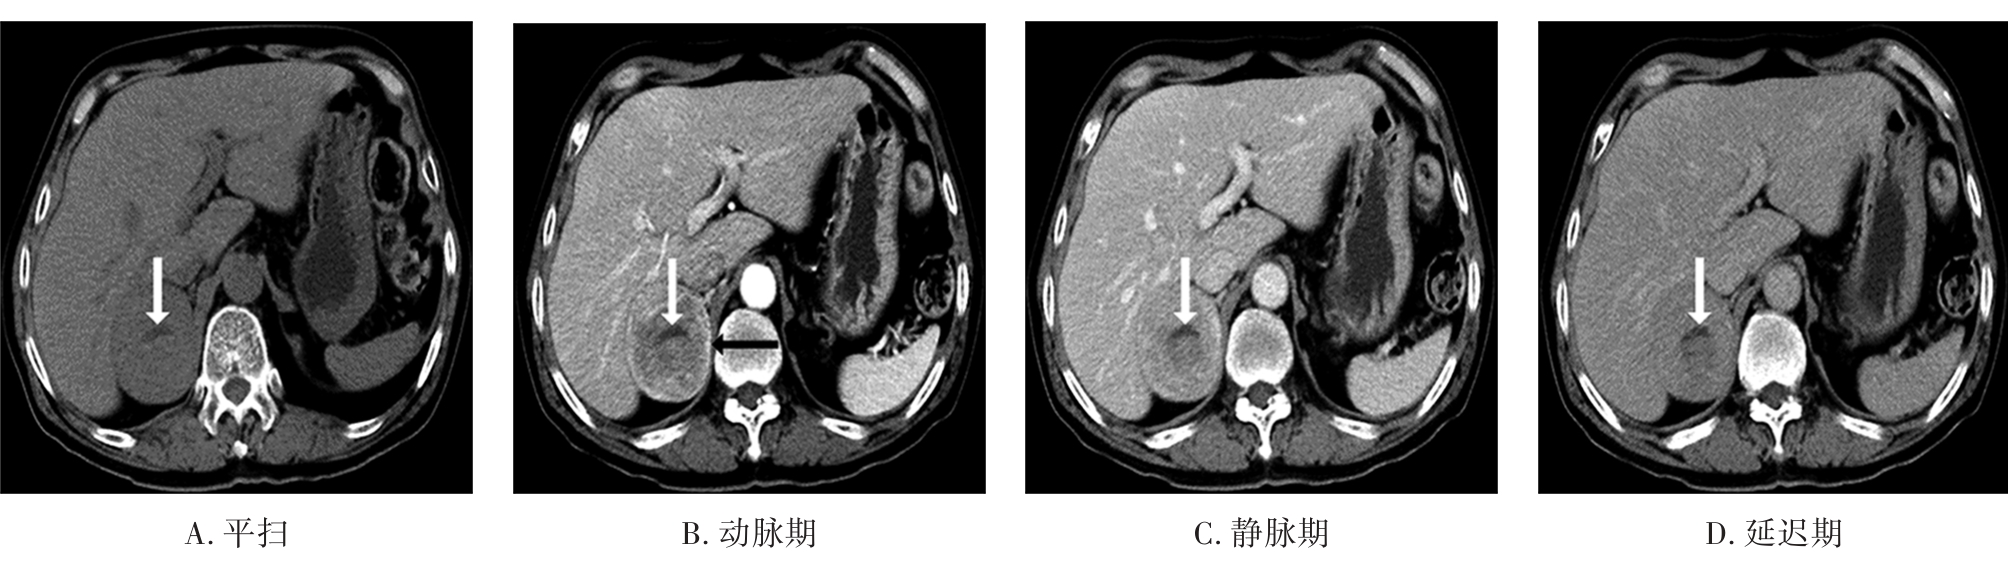

• 嗜铬细胞瘤及副神经节瘤不同生化表型的CT征象对比研究

2024, 49(2):203-209. DOI: 10.13406/j.cnki.cyxb.003433

摘要 (51) HTML (33) PDF 3.10 M (96) 评论 (0) 收藏

摘要:目的 分析生化阴性嗜铬细胞瘤及副神经节瘤(pheochromocytomas and paragangliomas,PPGLs)的电子计算机断层扫描(computed tomography,CT)征象是否有别于生化阳性PPGLs,同时了解生化阳性PPGLs不同表型的CT征象是否存在差异。方法 回顾性分析131例PPGLs患者的术前腹部增强CT图像,包括肿瘤位置、大小、形态、囊变坏死、液-液分层、钙化、向心结节状强化、肿瘤内粗大血管、强化包膜、绝对廓清率及相对廓清率。根据生化水平,将患者分为生化阳性组和阴性组,阳性组进一步分为去甲肾上腺素型、肾上腺素型及多巴胺型。比较各组及各表型间的CT征象差异。结果 相较于生化阴性组,阳性组PPGLs更大(Z=-2.064,P=0.039)、囊变坏死(χ2=6.610,P=0.010)及向心结节状强化(χ2=3.909,P=0.048)的比例更高;相较于去甲肾上腺素型,肾上腺素型PPGLs更大(Z=-2.036,P=0.042)、强化包膜比例更高(χ2=7.242,P=0.007)。结论 肿瘤大小、囊变坏死及向心结节状强化的CT征象有助于术前诊断生化阴性PPGLs,肿瘤大小及强化包膜有助于解释去甲肾上腺素型及肾上腺素型PPGLs不同临床表现产生的机制。